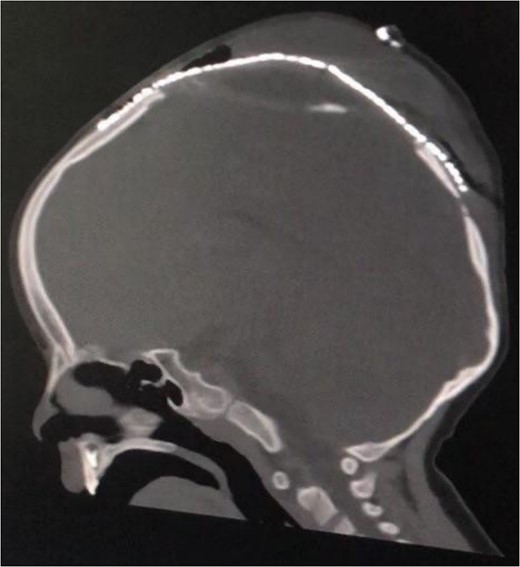

Upon seeking medical advice, the patient was found to have a left parietal pseudomeningocele and later he underwent a duraplasty with evacuation of the pseudomeningocele but months later, a bulge reappeared. Multiple follow ups were done through which CSF aspiration by needle was performed with the hope of CSF to stop spontaneously. At the age of 2 years, an external ventricular drain (EVD) was inserted without significant improvement and a complain of right arm and leg weakness was noticed, so he was referred to our hospital for further treatment. Hence, a CT scan was done (Fig. 2), revealing a median and left paramedian parietal encephalocele causing detorsion and compression of the sagittal sinus, and part of the primary motor area was extending into the encephalocele region.

Preoperative coronal (A) and sagittal (B) brain CT scan demonstrating the encephalocele.